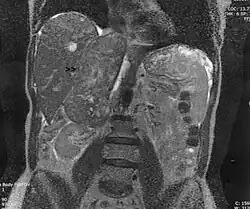

| Leiomyosarcoma of the adrenal vein. Coronal view of abdominal MRI. Tumor (arrow) extends from the superior pole of the right kidney to the right atrium. | |